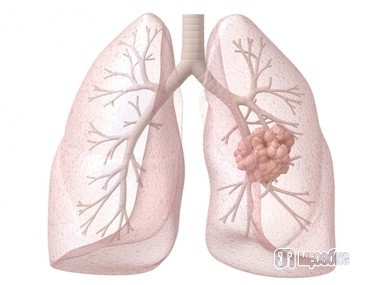

7. Ngăn ngừa ung thư phổi

Nghiên cứu chỉ ra rằng bưởi chùm cũng có thể ngăn ngừa và chống lại căn bệnh ung thư phổi. Mỗi ngày dùng ba ly, mỗi ly khoảng 170 gram bưởi chùm, đã được chứng minh rằng phương pháp này có thể đẩy lùi tác hại của khói thuốc lá và xì gà. Bưởi chùm kích hoạt các enzim chống lại căn bệnh chết người này. Bưởi chùm ruột hồng được chứng tỏ là có công dụng đặc biệt trong việc phòng ngừa bệnh ung thư phổi.